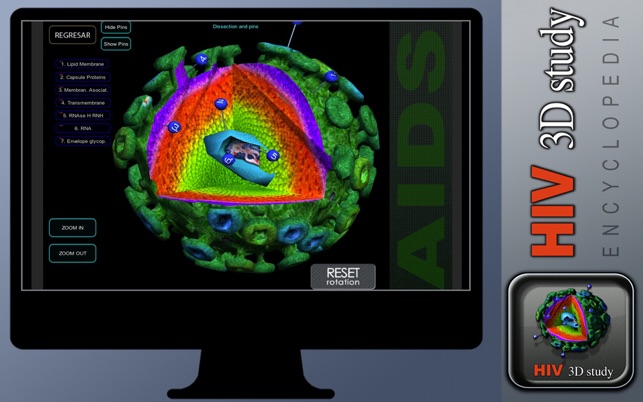

And of course a 3D cell with pins to show each part.

You can rotate on any direction with a mouse all 3D parts of the cell

Hid and show pins, Hide and show information screens on 3D zone.